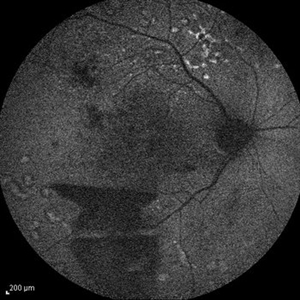

Idiopathic Occlusive Retinal Vasculitis (Late Stage) Idiopathic Occlusive Retinal Vasculitis (Late Stage)May 31 2014 by Hamid Ahmadieh, MD FAF image of the left eye of a 28-year-old woman with idiopathic occlusive retinal vasculitis 6 months after the onset. Patches of hard exudate are present superior to the fovea. Photographer: Elham Salehi, Negah Eye Center, Tehran Imaging device: Heidelberg Spectralis Condition/keywords: fundus autofluorescence (FAF)

Idiopathic Occlusive Retinal Vasculitis (Late Stage) Idiopathic Occlusive Retinal Vasculitis (Late Stage)May 31 2014 by Hamid Ahmadieh, MD Wide-field FA image of the left eye of a 28-year-old woman with idiopathic occlusive retinal vasculitis 6 months after the onset. Photographer: Elham Salehi, Negah Eye Center, Tehran Imaging device: Heidelberg Spectralis Condition/keywords: capillary closure, macular infarction